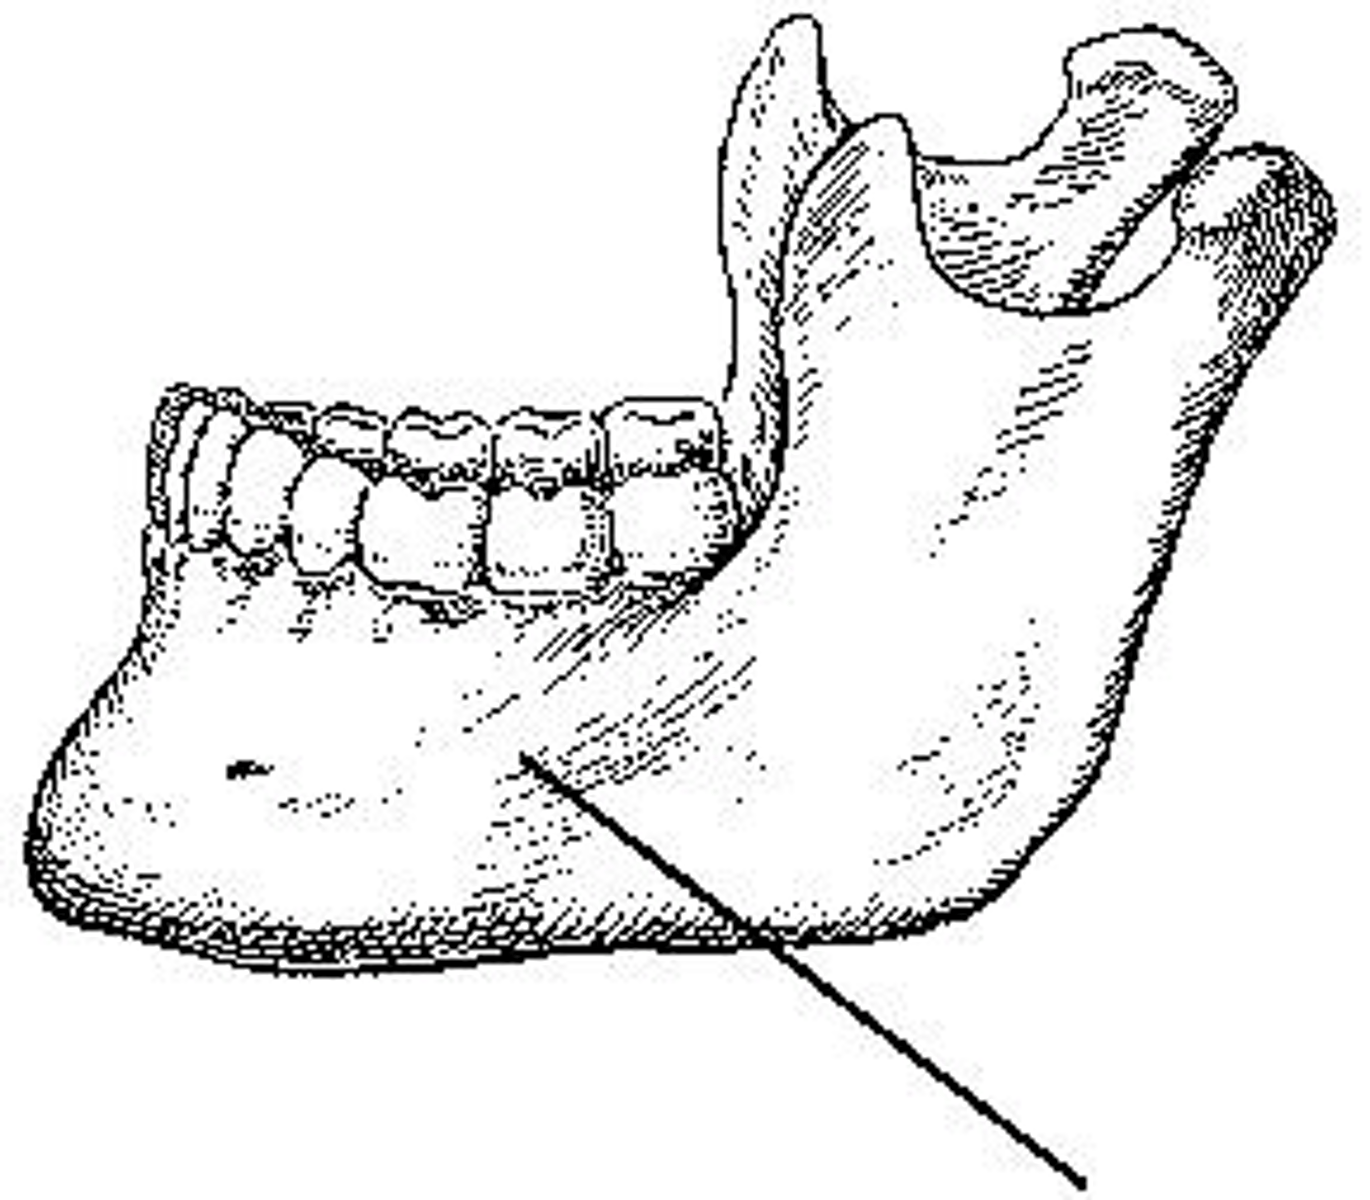

What part of the mandible is identified?

Body

What portion of the mandible is identified?

Ramus